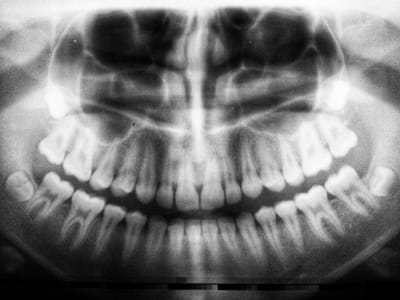

In this post, we discuss the NDEB AFK exam.